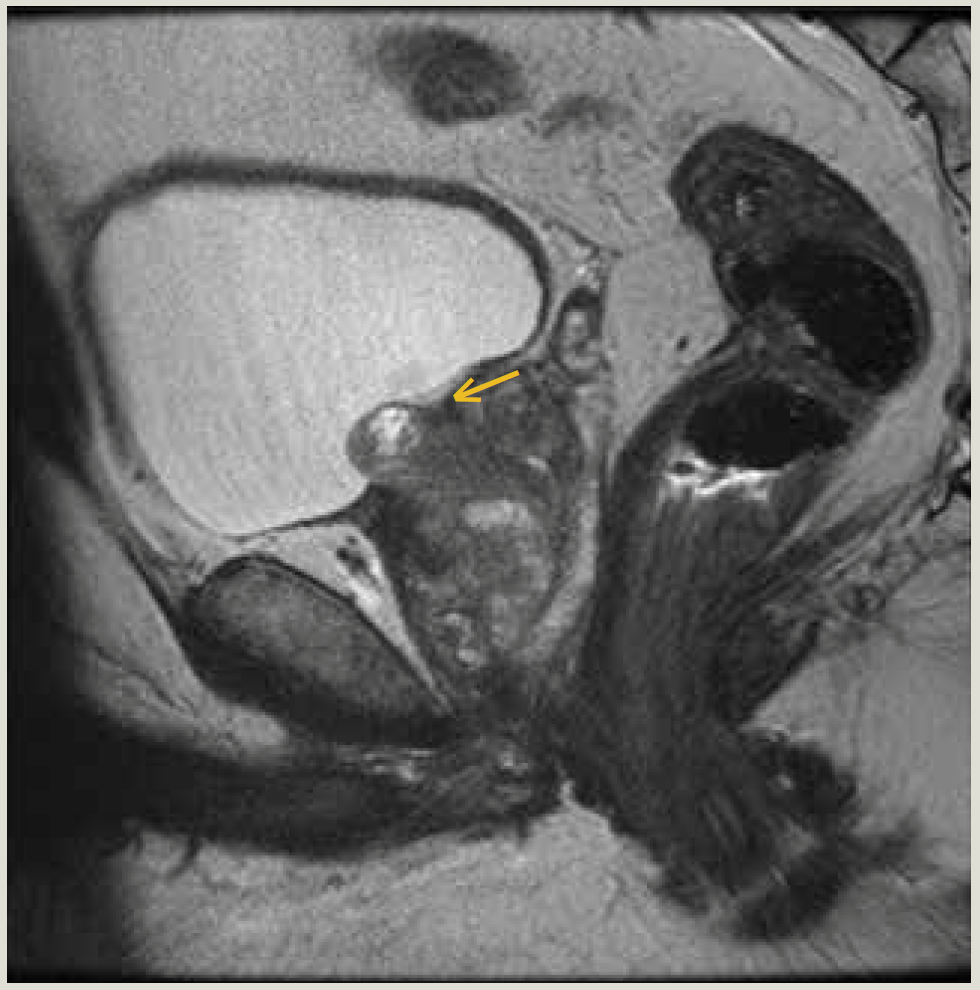

We present a male, aged 56 years, with an elevated prostate-specific antigen (PSA) of 6.2 who was found to have Gleason 6 PC on systematic biopsy. Approximately 6 months later, MRI identified a Prostate Image–Reporting and Data System (PI-RADS) 4 lesion in the right base to mid-gland transition zone, and targeted biopsy upstaged his cancer to Gleason 3 + 4 = 7 (Figure 1). After he consulted with numerous physicians, he underwent uncomplicated FLA of his prostate.

FIGURE 1. Sagittal T2 with PI-RADS-4 lesion in the right base to mid-gland transition zone (arrow).

PI-RADS, Prostate Image – Reporting and Data System.